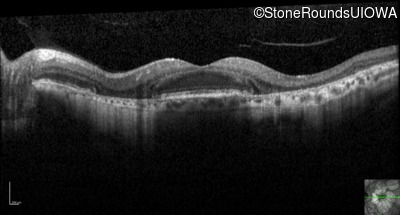

Optical Coherence Tomography - Right - 20/40 -2

Exemplar / OCT Stack

OCT Stack